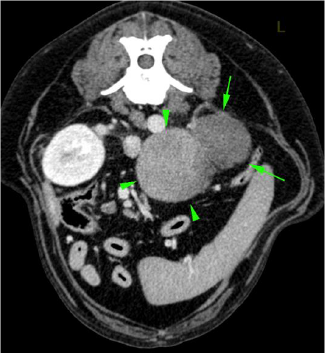

Im CT kann der Tumor bestätigt werden, bei der beobachteten Flüssigkeit handelt es sich um Blut. Eine Gewebepunktion diagnostiziert ein sogenanntes Phäochromozytom - ein Tumor der Nebenniere, welcher aus Zellen besteht, welche das Hormon Adrenalin produziert.

Phäochromozytome können in die hintere Hohlvene einwachsen, was die Entfernung massiv erschweren oder verunmöglichen kann. Bei Maylo wurde offensichtlich durch das Tumorwachstum ein Gefäss beschädigt, welches blutete und zum beobachteten Hämatom (Bluterguss) führte. Es ist denkbar, dass diese Blutung auch für die akuten Bauchschmerzen des Hundes verantwortlich war.